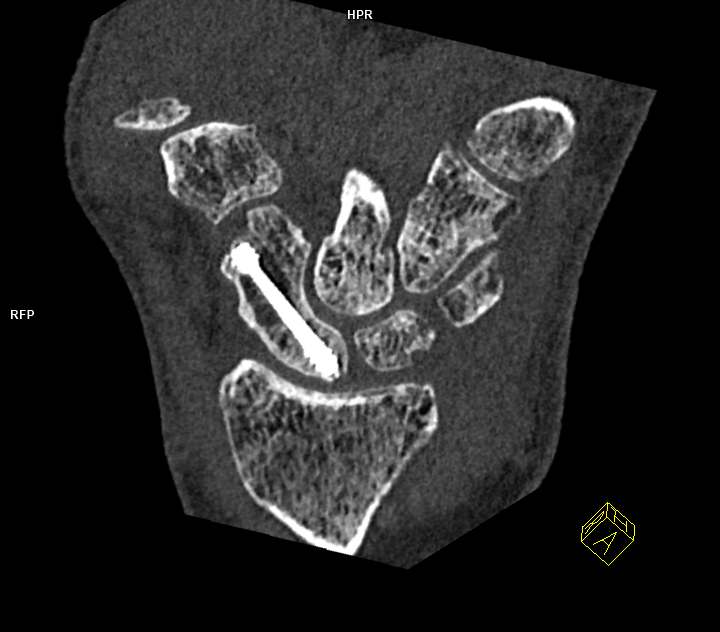

CT Aufnahme der Handwurzelknochen bei Zustand nach osteosynthetischer Versorgung einer Kahnbein-Fraktur.